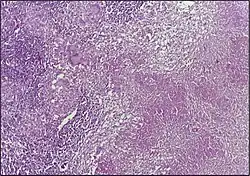

![]() |

Tuberculous granuloma | Caseating granulomatous lesion with areas of amorphous granular eosinophilic necrotic debris known as caseation (on the right half) bordered by collections of epitheloid cells, Langhan giant cells and lymphocytes. | Category: Histopathology of tuberculous granuloma | Tuberculous granuloma |